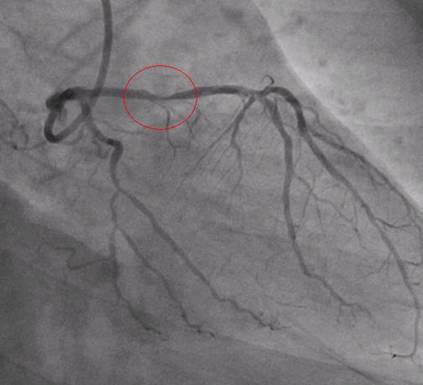

Once they identified the major block they have done immediately a procedure called angioplasty along with 2 Stints, mean they will insert a foreign body into the heart arteries and open the blocked area of arteries. Please see the below image after the procedure.